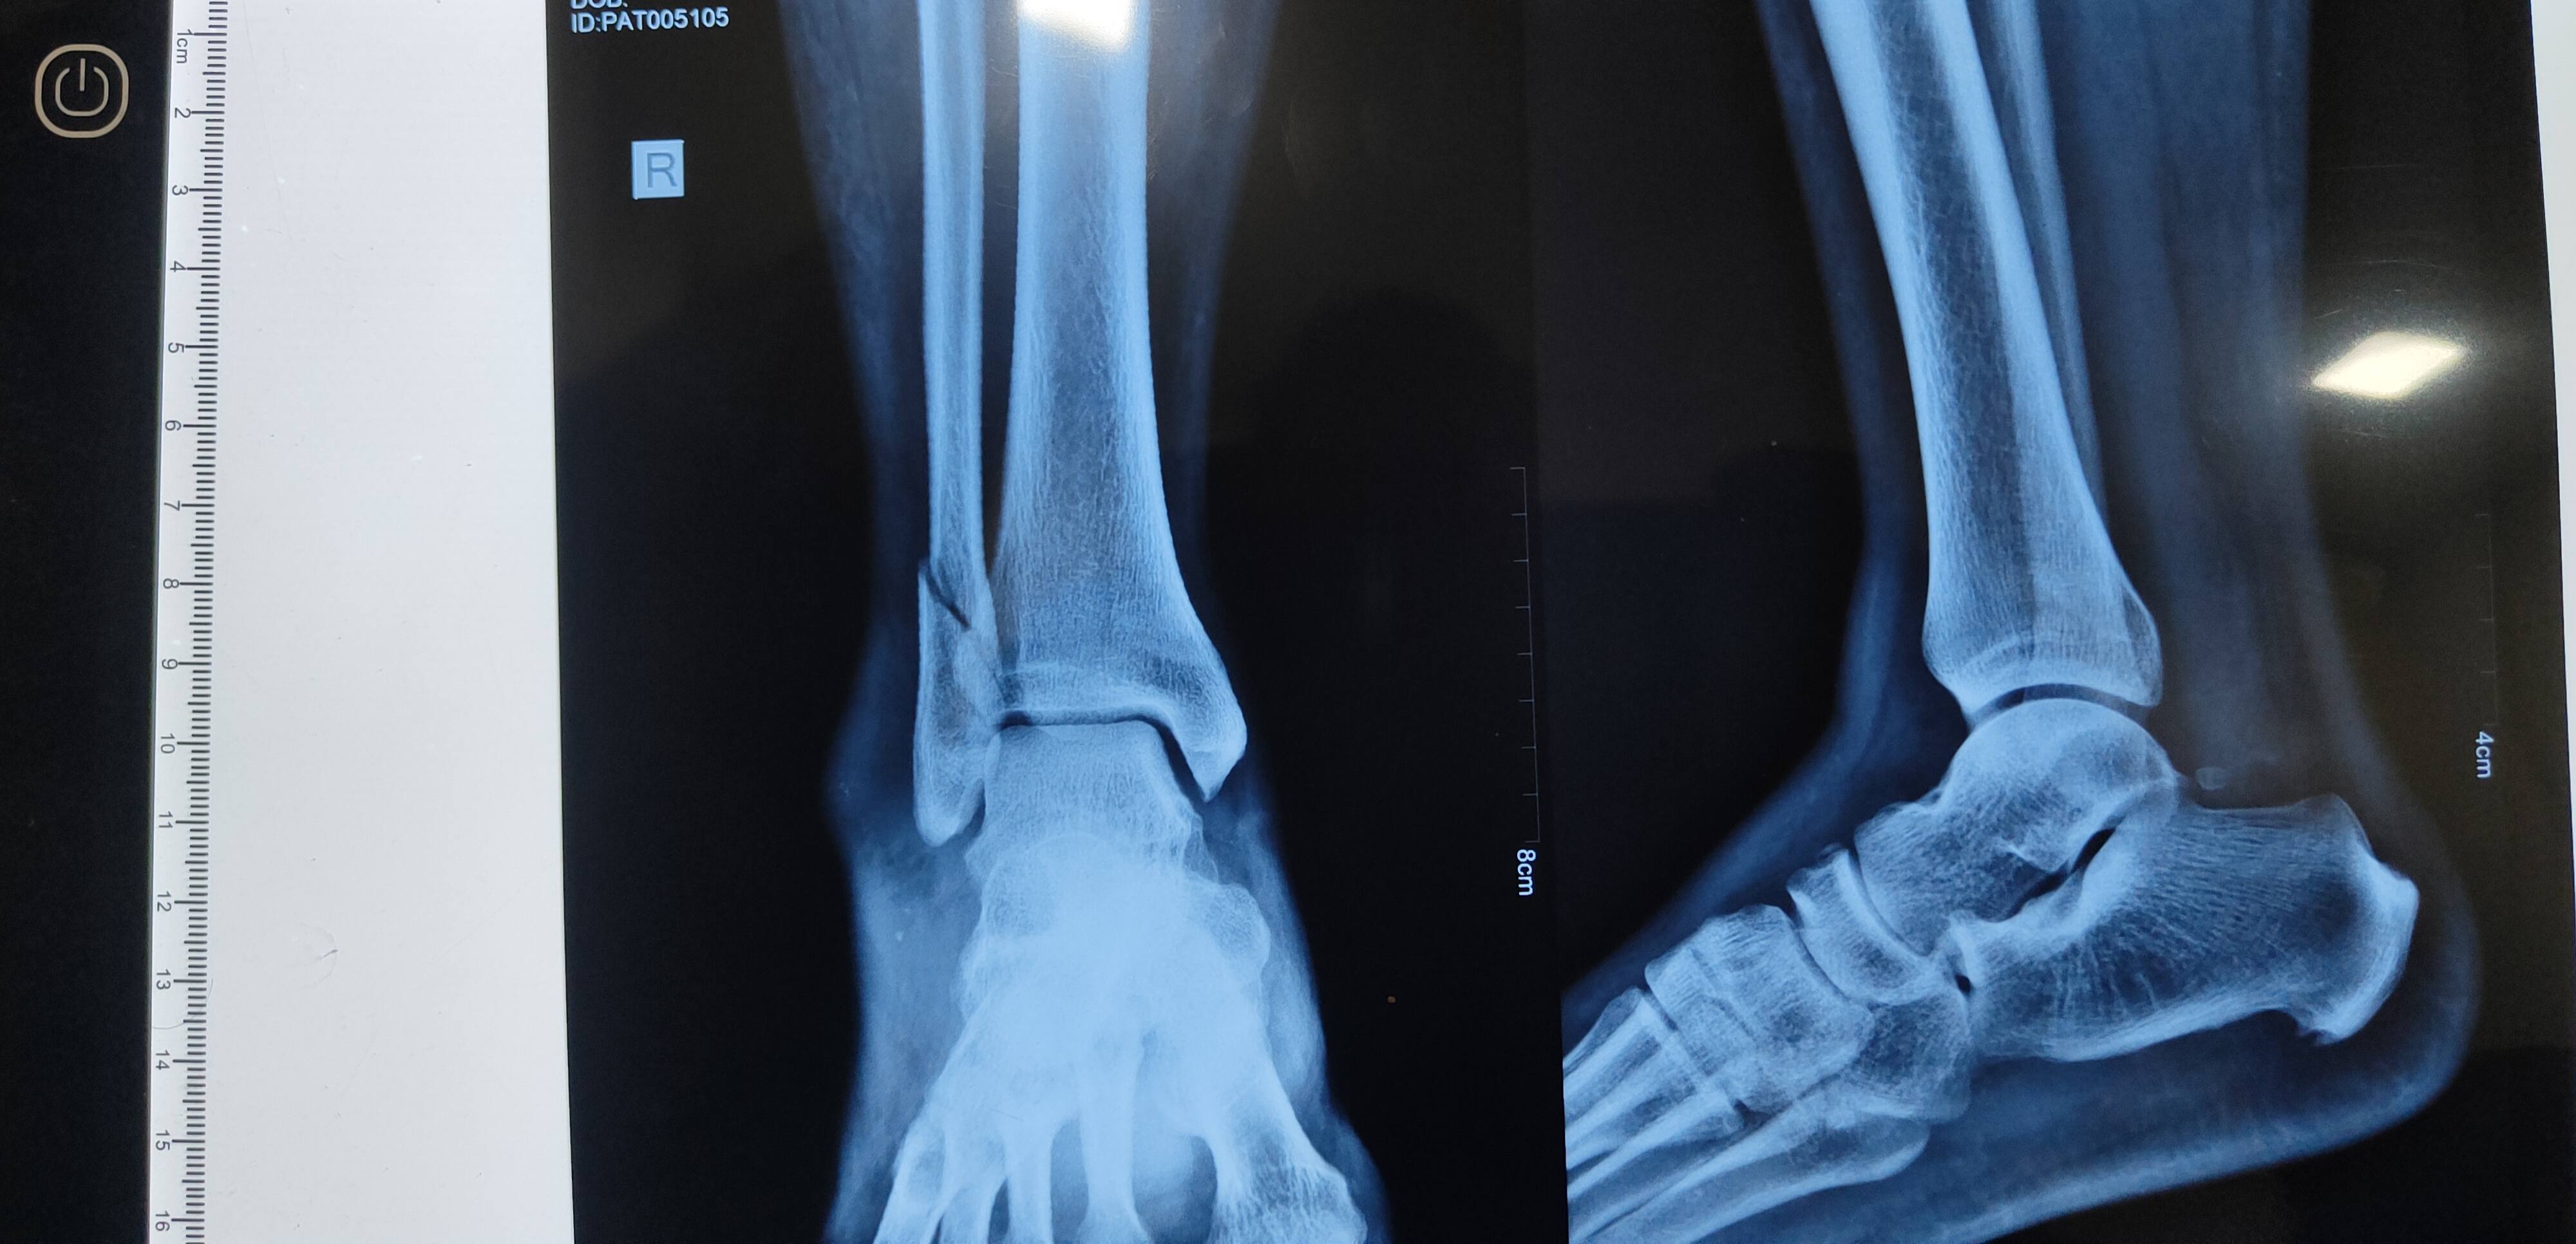

Sprain issue please advice...

Vaibhav patil